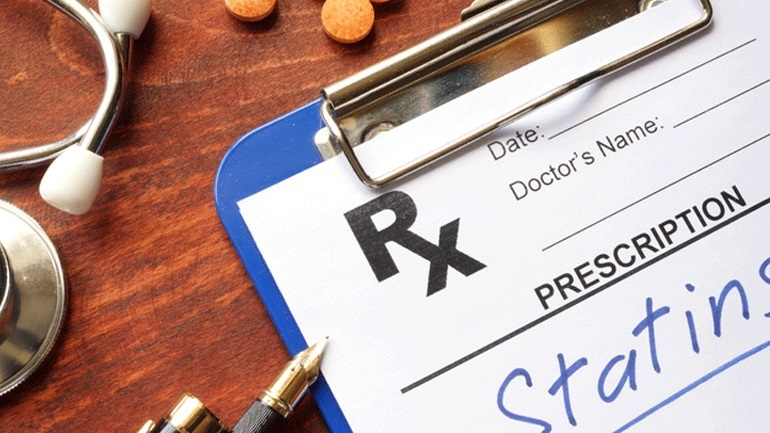

Βακτήρια του εντέρου συνδέονται με χαμηλότερο κίνδυνο καρδιακής νόσου

Οι αλλαγές στο μικροβίωμα του εντέρου συνδέονται επιπλέον με μια σειρά ασθενειών, όπως ο διαβήτης τύπου 2, η παχυσαρκία και η φλεγμονώδης νόσος του εντέρου.